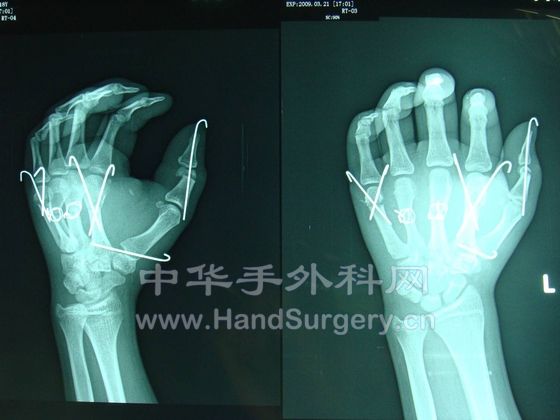

一个断掌+5个断指,显示我科实力!

我这里有术后半年的手术图片,发上来给大家看看,我们曾作出了手外科功能最好的多指离断!